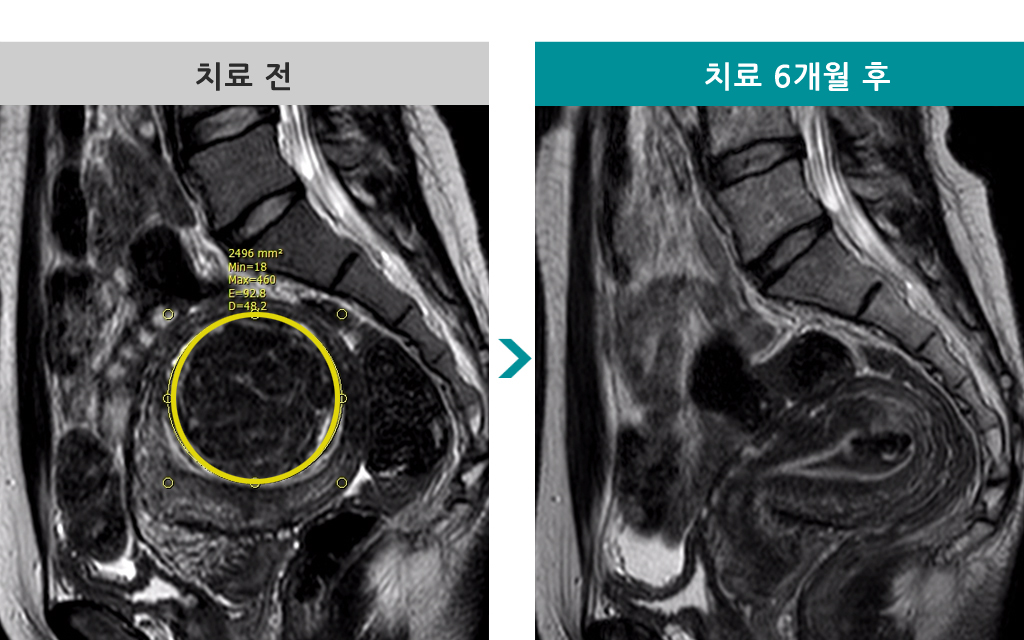

자궁근종통합센터

48세 [자궁선근증 색전술] 전후 MRI사진 비교 - 선근증 부피 60% 감소